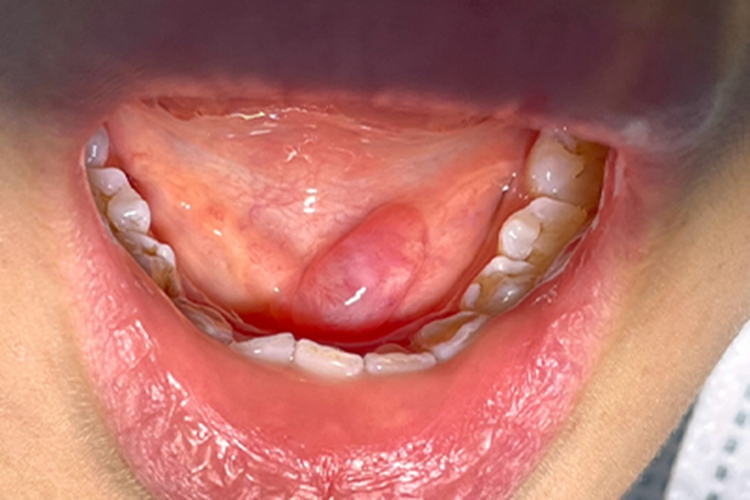

舌下腺囊肿可发生在患者口腔,表现为椭圆形的鼓包,触之较软,与周围界限清晰,检查见其位于黏膜与肌肉之间,没有疼痛感。

舌下腺囊肿主要由于外渗性黏液囊肿、舌下腺受伤后导管破裂,黏液外渗入组织间隙所致。